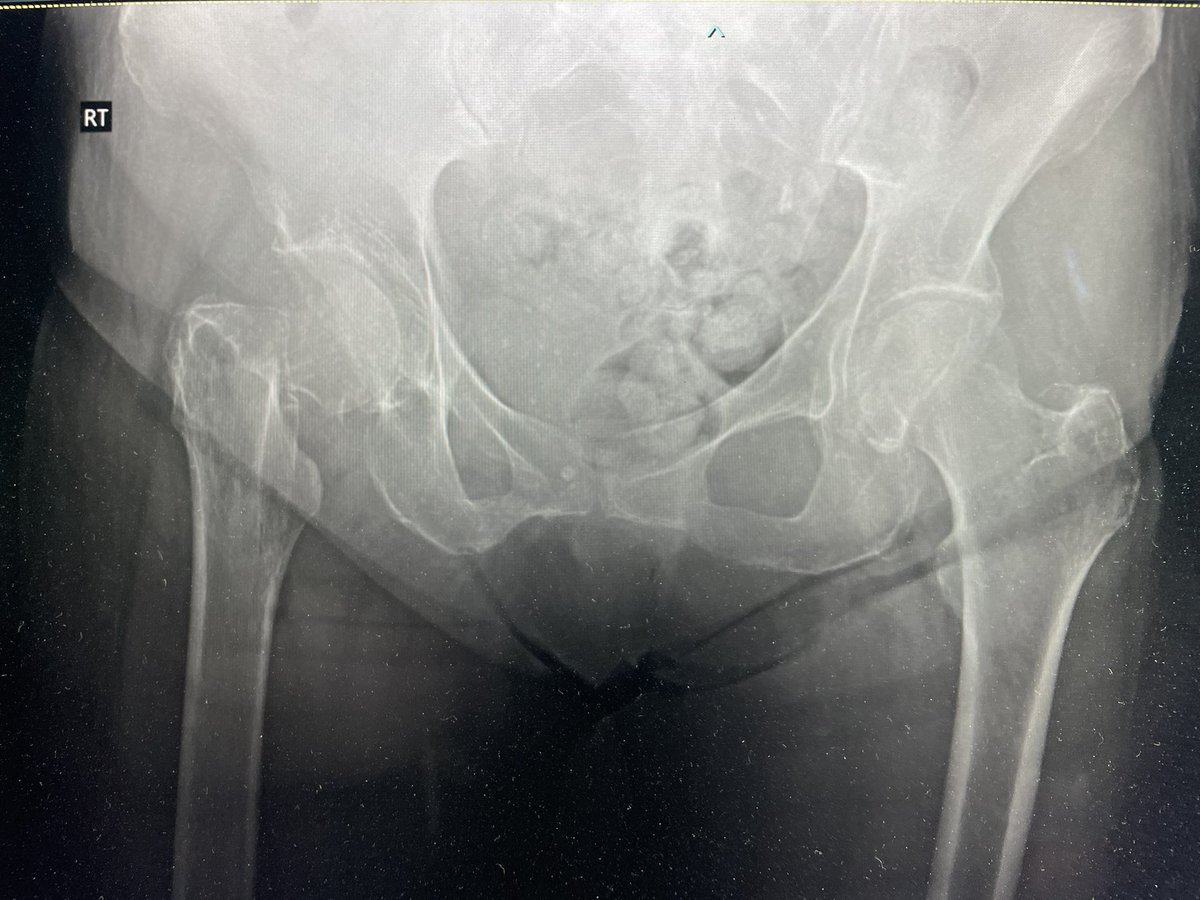

85 yo F. Healthy and active. Lives at home and walks with no aid. Knocked over by an animal and has this femoral neck fracture.

What do you do? @drsebheaven @BrianChalmersMD @FixnBones @jointdocShields @DrMarecek @CE_HandSurg @drs462 @CenterRotation @rkh_md @ExeterHipUnit